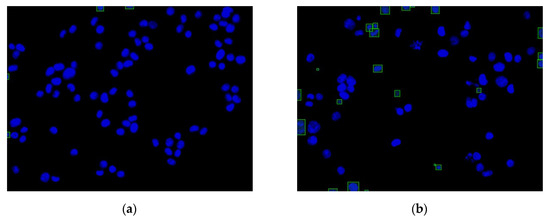

3.2. Regions without Cytoskeleton Removal and Regions with Incomplete Nucleus Images in the Boundary

Figure 13 shows the function of each step in this experiment. The images of the cell nuclei and cytoskeleton are shown in Figure 13, which is separated from Figure 9. We used k-means clustering [38] for the color quantization of blue elements in the images (the number of quantized colors, k = 15). The background was then removed to obtain the cell nucleus regions, and the lowest quantized color grayscale value was used as the background color. The regions with values higher than the background color are considered to be the cell nucleus and cytoskeleton regions. Figure 13 shows the results: Figure 13a1–a4 show the images after color quantization, while Figure 13b1–b4 show the cell nucleus and cytoskeleton regions after the background is removed. We used the cytoskeleton region (N) to obtain the valid cell nucleus regions (N∩C), and the results are shown in Figure 14. After the P (=N−B−D) operation, no valid regions were present in Figure 14a (the four regions are located at the edges of the image). However, Figure 14b contains 10 invalid regions, and 12 regions are located at the edges of the image (rectangular box with diagonal lines).

Figure 14.

Invalid nucleus regions and regions in boundary detection by P (=N-B-D) operation (rectangular box with diagonal lines): (a) HCT116 cell with DMSO (no.4484); (b) HCT116 cell with dinaciclib (no.4496).